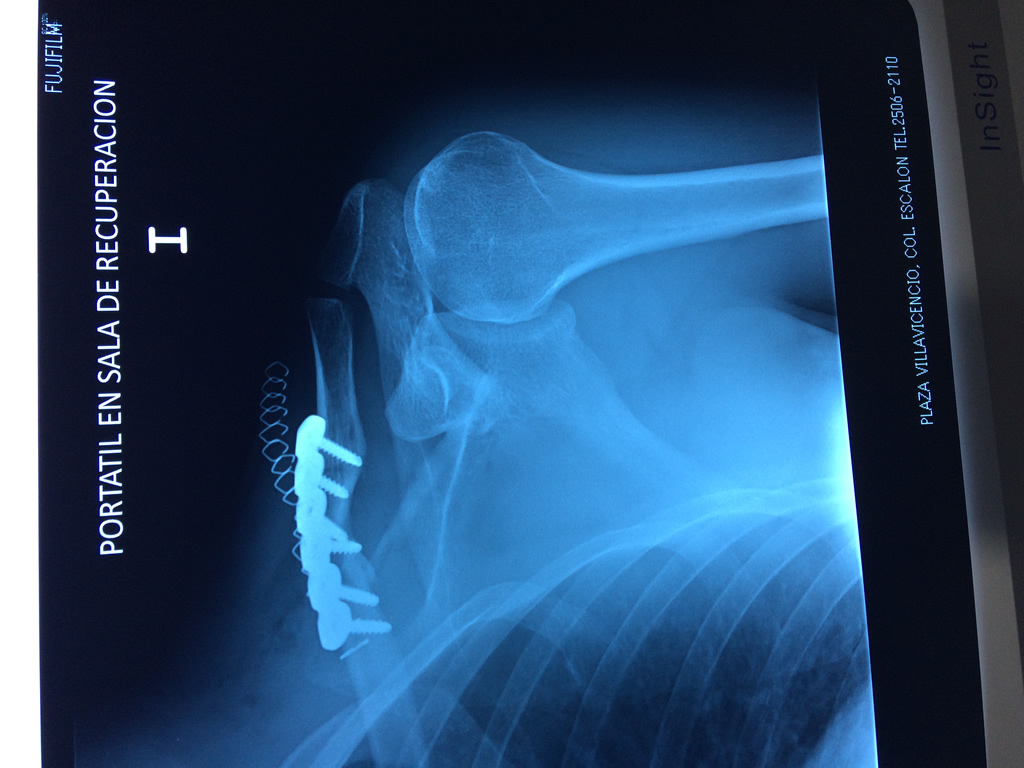

La clavícula es un hueso largo, con forma de "S" itálica, situado en la parte anterosuperior del tórax. Junto con la escápula forman la cintura escapular. Se puede palpar por toda su longitud y se extiende del esternón al acromion de la escápula, siguiendo una dirección oblicua lateral y posterior.

Se considera el único medio de unión entre el miembro superior y el tórax. A pesar de su aspecto, similar al de un hueso largo, posee una estructura semejante a la de un hueso plano, ya que carece de epífisis y de diáfisis, lo que la harían entrar dentro de la clasificación de hueso largo. Carece de un canal medular propiamente dicho.